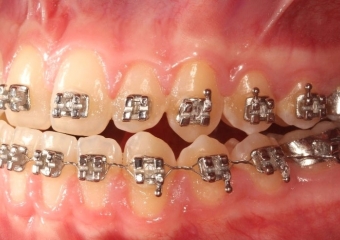

Mordida após a cirurgia - Clínica Cliniface

Mordida após a cirurgia